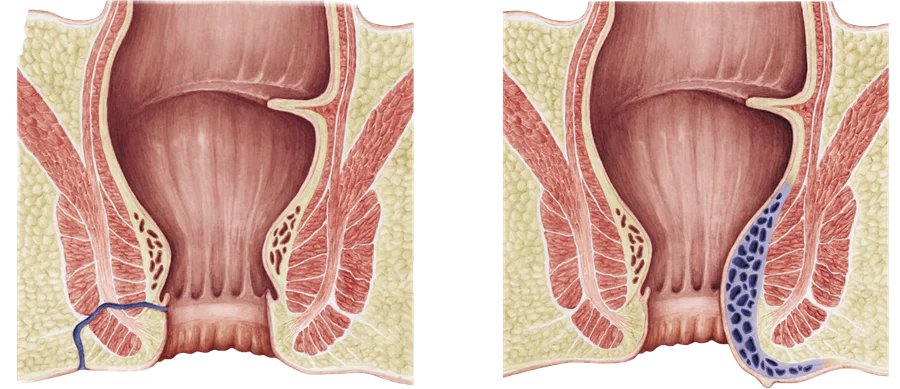

The term Proctology refers to varied surgical procedures performed on the colon, anus, and rectum. Medical professionals performing such procedures are referred to as coloproctologists or colorectal surgeons. These surgeons treat various disorders like anal fissures (abnormal tears or cracks within the patient’s anus), birth defects within the anus or colon, swelling and inflammation of veins in the rectum (also referred to as haemorrhoids), anorectal fistulas (passageways that connect different parts of the anorectal area to the surface of the skin), faecal incontinence, colon and rectal cancers, anal or rectal prolapse, diverticular disease, diverticulitis, anus and other birth defects, Crohn’s disease and other severe colic disorders, and anal cancer.

- Haemorrhoids